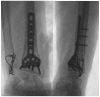

Distal radioulnar joint (DRUJ) instability is a complex condition that can severely affect forearm function, causing pain, limited range of motion, and reduced strength. This review aims to consolidate current knowledge on the diagnosis and management of DRUJ instability, emphasizing a new classification system that we propose. The review synthesizes anatomical and biomechanical factors essential for DRUJ stability, focusing on the interrelationship between the bones and surrounding soft tissues. Our methodology involved a thorough examination of recent studies, incorporating clinical assessments and advanced imaging techniques such as MRI, ultrasound, and dynamic CT. This approach allowed us to develop a classification system that categorizes DRUJ injuries into three distinct grades. This system is intended to be practical for both clinical and radiological evaluations, offering clear guidance for treatment based on injury severity. The review discusses a range of treatment options, from conservative measures like splinting and physiotherapy to surgical procedures, including arthroscopy and DRUJ arthroplasty. The proposed classification system enhances the accuracy of diagnosis and supports more effective decision making in clinical practice. In summary, our findings suggest that the integration of advanced imaging techniques with minimally invasive surgical interventions can lead to better outcomes for patients. This review serves as a valuable resource for clinicians, providing a structured approach to managing DRUJ instability and improving patient care through the implementation of our new classification system.